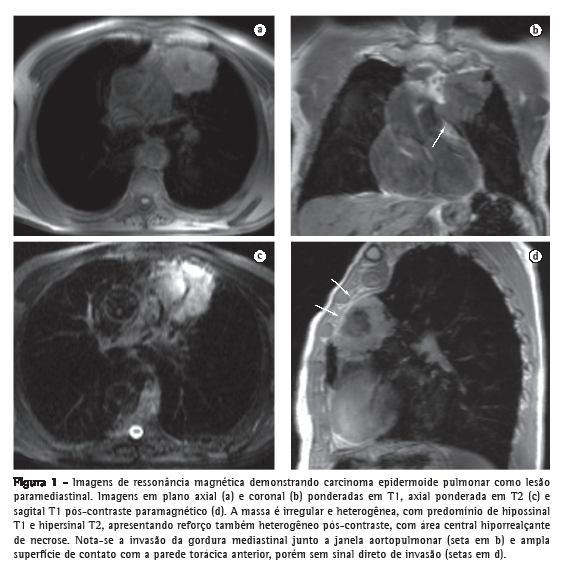

Em geral, o carcinoma broncogênico aparece nas imagens de RM como lesão sólida irregular, de hipointensa a isointensa na ponderação em T1 e hiperintensa em T2, com realce intenso após a administração do contraste, sendo heterogêneo nas lesões maiores devido a áreas de necrose central. Mesmo nas lesões fora do sulco superior, a RM pode ser melhor na identificação da invasão direta das estruturas adjacentes pela neoplasia (Figura 1), incluindo o mediastino (janela aortopulmonar e demais espaços), traqueia, brônquios, parede torácica, diafragma (tumores dos ângulos costofrênico e cardiofrênico), coração (invasão do pericárdio ou miocárdio) e grandes vasos (aorta e artérias pulmonares).Na diferenciação entre os tumores classificados como T3 ou T4, a sensibilidade da RM é semelhante à da TC, mas a RM tem maior acurácia na identificação da invasão mediastinal e hilar. Sequências dinâmicas de cine-RM podem aumentar a especificidade na detecção da invasão da parede torácica e do pericárdio. Na detecção de linfonodos mediastinais suspeitos para metástases, novas técnicas de RM têm aumentado a sensibilidade do exame. A sequência short inversion time (TI) inversion recovery (técnica T2 com supressão de gordura por inversão e recuperação) permite diferenciar entre os linfonodos metastáticos e não metastáticos em pacientes com tumores não pequenas células, sendo os primeiros mais hiperintensos e com maior sinal T2.(12-15)